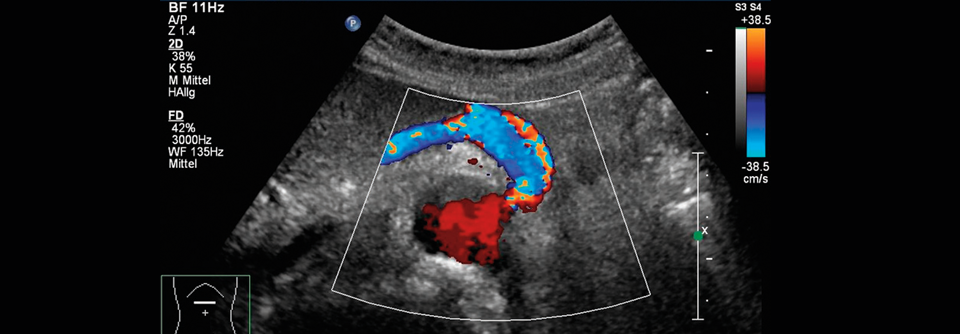

Die chronische mesenteriale Ischämie (CMI) entsteht aufgrund von Stenosen oder chronischen Verschlüssen des Truncus coeliacus, der A. mesenterica superior und inferior. Die häufigste Ursache sind athero­sklerotische Plaques (> 90 %). Rauchen, Hypertonie, Dyslipid­ämie sowie hohes Lebensalter begünstigen die Entstehung. Frauen sind häufiger betroffen als Männer.

Meist kompensieren Anastomosen zwischen den Gefäßterritorien selbst hochgradige Stenosen oder Verschlüsse, sodass die Erkrankung symptomlos bleibt und nur zufällig entdeckt wird. Die Prävalenz der asymptomatischen CMI wird bei Erwachsenen auf 14–15 % geschätzt. Bei Patienten mit PAVK oder abdominellem Aortenaneurysma findet sie…